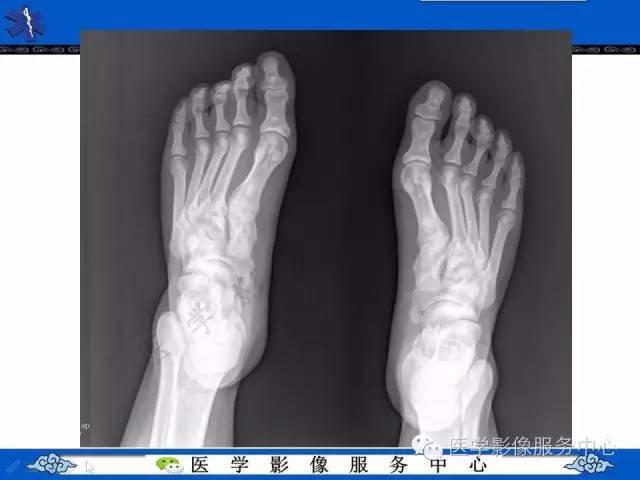

【PPT】石骨症——少见的骨病例,但是过目不忘!